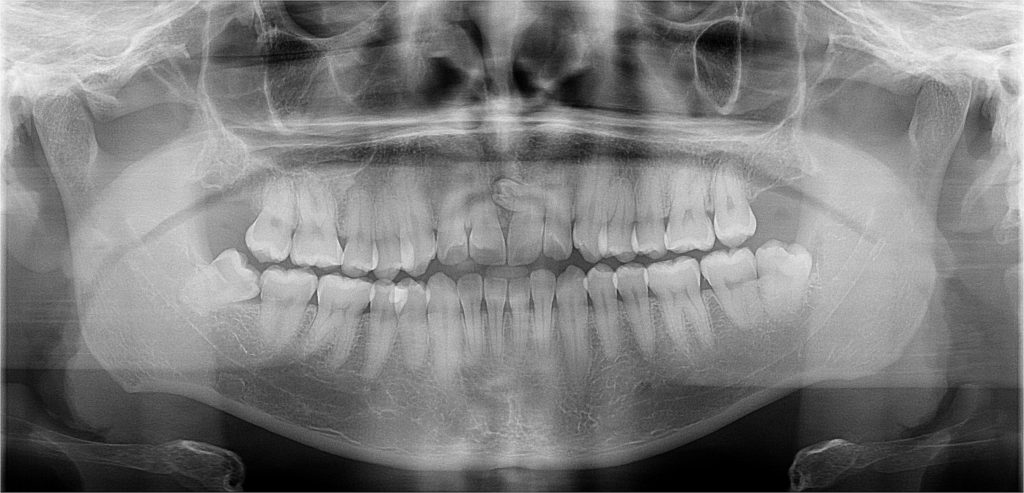

Contamos con el primer y único equipo de Rayos X digital de la ciudad.

Para diagnosticar y tratar las enfermedades orales de manera más eficaz y precisa a nuestros pacientes, y así otorgarles una atención integral y segura, evitándoles viajar cientos de kilómetros a otras ciudades para la toma de estos exámenes. Nuestro equipo de rayos x cuenta con todas las autorizaciones sanitarias para su instalación y desempeño.